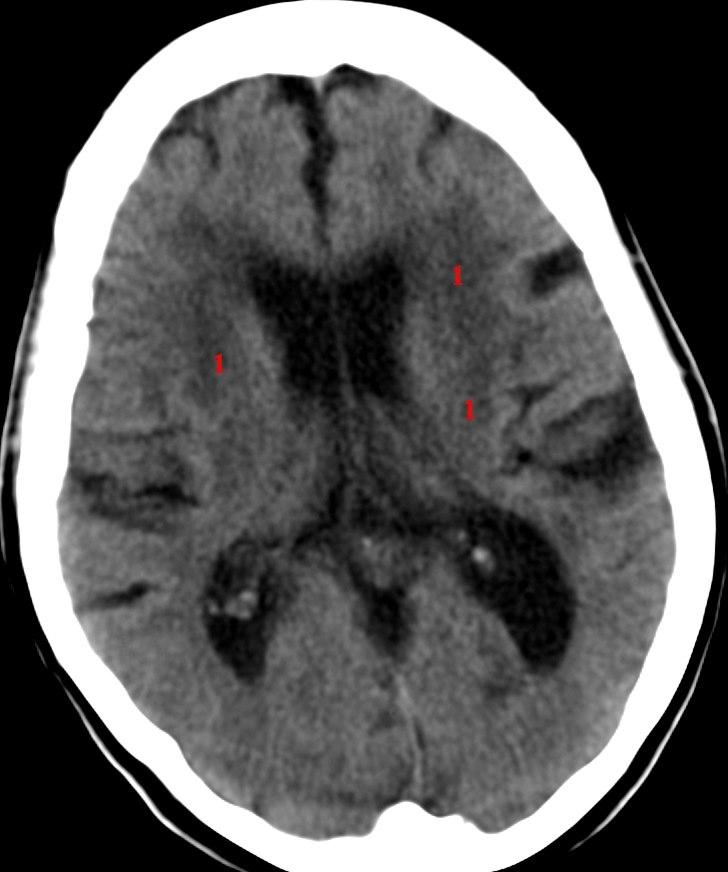

Sykehistorien og eventuelle funn ved legeundersøkelsen vil gi mistanke om at noe er galt i hjernen. CT av hjernen vil i første omgang være den avgjørende undersøkelsen for å avdekke eventuell hjerneskade eller hjernesvinn. Ved behov for mer detaljert diagnostikk kan MR av hjernen bli aktuelt. Andre tilleggsundersøkelser kan være blodprøver, nevropsykologiske tester, EEG, lumbalpunksjon, CT-PET.